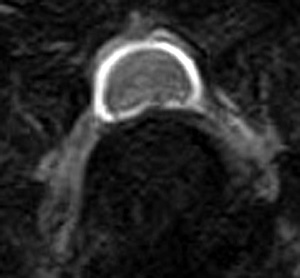

5~6歳以上の去勢手術をしていないオス犬に多い病気ですが、メス犬や去勢した犬に起こることもあります。お尻の筋肉が萎縮した結果、筋肉の隙間から直腸や膀胱が皮膚の下にとびでてしまいます。これにより便が出にくくなったり膀胱炎になったりします。手術をすることで機能回復および今後の致死的な状況を回避することができます。当院では去勢手術→結腸固定→前立腺固定→骨盤隔膜構成筋の縫縮→内閉鎖筋フラップ→浅臀筋フラップの順で通常腹側・臀部左右両側同時に行います。また老化以外に、筋肉が萎縮する原因があったり、腹圧がかかる原因があったりする場合も多いので、再発防止のためそれらの診断・治療も重要です。今回のワンちゃんも無事手術も終わり元気に退院しました。よかったね。